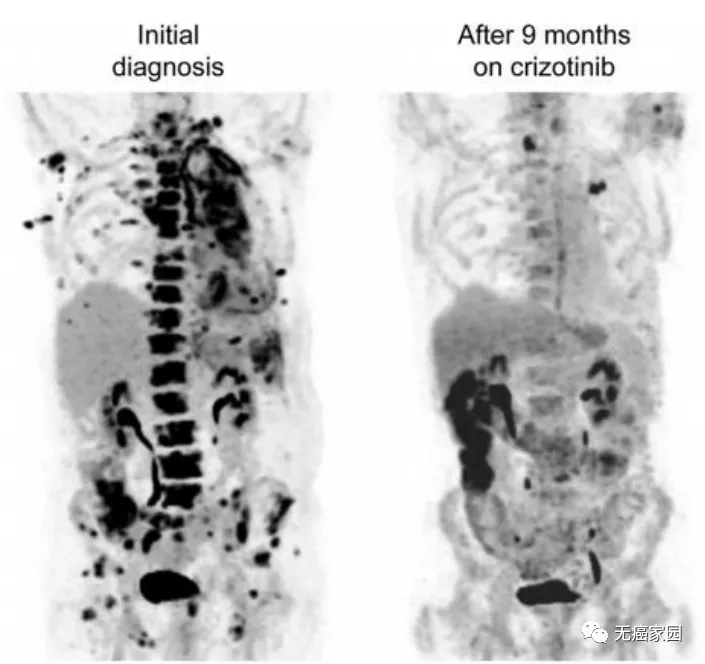

这是一名75岁的不吸烟男性患者,被诊断为转移性肺腺癌,携带MET 14外显子突变,无其他靶向致癌突变。在初诊时患者的左肺、胸膜、淋巴结、骨和软组织存在广泛转移。在使用克唑替尼治疗9个月后,胸部、腹部和盆骨疾病部位出现明显反应,达到显著缓解。

图为患者初诊(左)及克唑替尼治疗9个月后(右)对比图